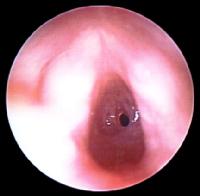

Subglottic Stenosis (SGS): The subglottic airway is narrowest part of the airway. This is because it is a complete, nonexpandable, and nonpliable ring, unlike the trachea, which has a posterior membranous section, and the larynx, which has a posterior muscular section. Congential SGS is diagnosed in the first few months of life after a persistent inspiratory stridor is heard. Acquired SGS is usually due to prolonged endotracheal intubation in premature babies. In most cases the symptoms usually resolve in the first few years of life.

4month old with SGS born at 26/40 and had 3months of ETT intubation. (Courtesy of emedicine.medscape.com)